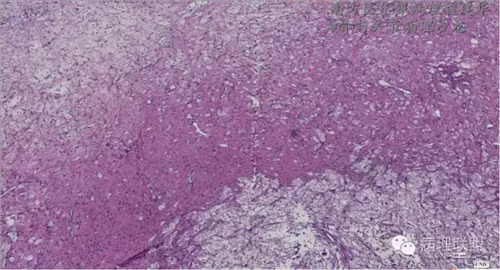

来源于组织细胞的相似性骨病ECD vs RDD 看图说话

病例由南方医华银病理魏建华提供,致谢。